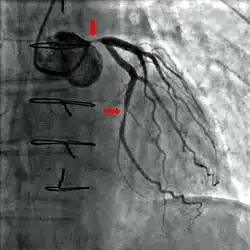

Coronary catheterization is one of the several cardiology diagnostic tests and procedures. Specifically, through the injection of a liquid radiocontrast agent and illumination with X-rays,[1] angiocardiography allows the recognition of occlusion, stenosis, restenosis, thrombosis or aneurysmal enlargement of the coronary artery lumens; heart chamber size; heart muscle contraction performance; and some aspects of heart valve function. Important internal heart and lung blood pressures, not measurable from outside the body, can be accurately measured during the test. The relevant problems that the test deals with most commonly occur as a result of advanced atherosclerosis – atheroma activity within the wall of the coronary arteries. Less frequently, valvular, heart muscle, or arrhythmia issues are the primary focus of the test.

During coronary catheterization (often referred to as a "cath" or "cardiac cath" by physicians), blood pressures are recorded and fluoroscopy (X-ray motion picture) shadow-grams of the blood inside the coronary arteries are recorded. In order to create the X-ray pictures, a physician guides a small tube-like device called a catheter, typically ~2.0 mm (6-French) in diameter, through the large arteries of the body until the tip is just within the opening of one of the coronary arteries. By design, the catheter is smaller than the lumen of the artery it is placed in; internal (intra-arterial) blood pressures are monitored through the catheter to verify that the catheter does not block blood flow (as indicated by "dampening" of the blood pressure).

The catheter is itself designed to be radiodense for visibility and it allows a clear, watery, blood compatible radiocontrast agent, commonly called an X-ray dye, to be selectively injected and mixed with the blood flowing within the artery. Typically 3–8 cc of the radiocontrast agent is injected for each image to make the blood flow visible for about 3–5 seconds as the radiocontrast agent is rapidly washed away into the coronary capillaries and then coronary veins. Without the X-ray dye injection, the blood and surrounding heart tissues appear, on X-ray, as only a mildly-shape-changing, otherwise uniform water density mass; no details of the blood and internal organ structure are discernible. The radiocontrast within the blood allows visualization of the blood flow within the arteries or heart chambers, depending on where it is injected.

If atheroma, or clots, are protruding into the lumen, producing narrowing, the narrowing may be seen instead as increased haziness within the X-ray shadow images of the blood/dye column within that portion of the artery; this is as compared to adjacent, presumed healthier, less stenotic areas.